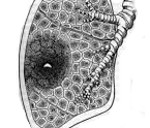

J85.3 Абсцесс средостения

Описание

Нет подробного описания, смотрите связи